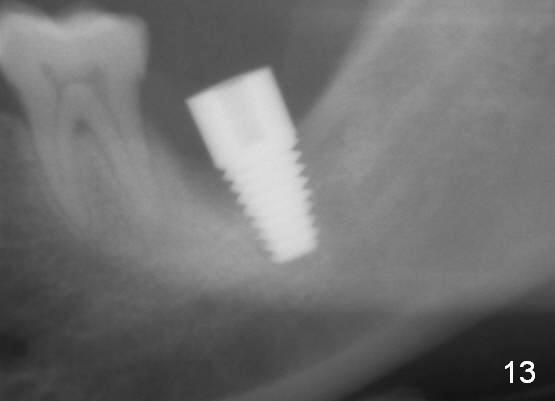

The lower left 2nd molar of a 45-year-old lady has perio-endo disease (Fig.1). The patient is not only very nervous, but also active in gag reflex. It is difficult to take good preop PA (Fig.1 *: ). Root canal therapy is performed. A relatively good PA is taken 1 year postop, again due to gap reflex (Fig.2). The tooth is still nonsalvageable (Fig.3). The last PA is taken 3.5 years before extraction and immediate implant. Infiltration anesthesia is administrated first. The patient experiences pain during early stage of osteotomy, but she does not report readily. Block anesthesia is added. Intraop PAs are taken with difficulty (Fig.4,5 with #1 sensor; 5 mm tap in place). Invasion of the inferior alveolar canal is not noted (Fig.5 dashed line). Oozing is a little more than expected. This is ignored. A 7x14 mm tapered implant is placed; the upper border of the inferior alveolar canal is not intact (Fig.6). Paresthesia area is defined next day (Fig.7). The implant is reversed for a few turns. Paresthesia area is reduced 19 days later (Fig.8). The implant is not stable. Follow up PAs are taken with difficulty (Fig.9-11). It appears that a shorter cylindrical implant is more appropriate for this case (Fig.11). The implant is stabilized with splinting with questionable result (Fig.12).

There is bone growth in the mesial socket 1 year postop (Fig.14, as compared to Fig.13 (immediately postop, before back up). Mild paresthesia remains 2 years postop.